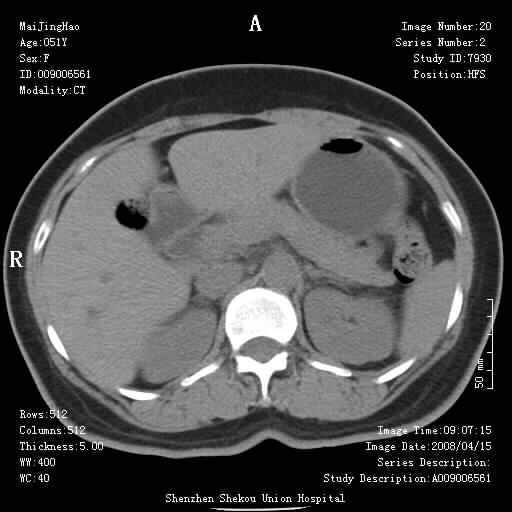

以下是引用余辉在2008-4-26 8:55:00的发言:[br]患者有结石史,此次腹痛4小时,胆总管全程扩张,应有胆总管末端梗阻,此次仍考虑胆结石症,积气不外两种原因,一种是结石下移时肠道内气体逸入,其次为产气菌感染。(倒数第三幅图像于扩张之胆总管末端似可见稍高密度影,考虑为结石影)

以下是引用听蝉观竹在2008-4-26 14:21:00的发言:[br]这个病例许多人认为“胰头增大”,那么到底胰头增大的标准是什么呢?

以下是引用听蝉观竹在2008-4-27 10:10:00的发言:[br]关于胰头大小问题有几种测量方法和正常值:[br][br]1、直量法:横径<4cm;[br]2、胰头横径与相邻层面椎体横径的比值为二分之一,超过椎体横径就提示胰头增大;[br]3、正常组成年人肠系膜上动、静脉水平夹角正常值范围为4.9°~34.7°大于35°提示胰头增大。[br][br]上述方法只是一种具体的判断,是“量”的评估,更重要的是“质”的评估:一是观察边缘是否光滑,有无局部隆起,有无分叶;二是观察密度(增强,尤其在动脉期和门脉期)是否均匀。[br][br]所以对于胰头是否有异常不仅仅是是目测可以解决问题的,不要轻易就说“胰头增大”。还有一个问题就是测量胰头应该在增强ct上进行,这样可以避免将血管测量进去。[br][br]为什么啰嗦讲怎么多,因为我们实际工作中同样存在影像科医生和临床医生动不动就说胰头增大,说是胰头癌。大家看看是不是这种情况?[br][br] 我个人观点-----本病例的胰头不增大。[br][br][本贴已被 听蝉观竹 于 2008-4-27 10:12:41 修改过]